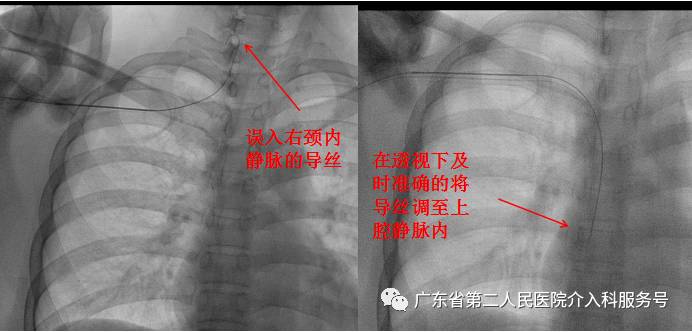

B.穿刺送入导丝后透视,可及时的发现误入右颈内静脉的导丝,并可在透视下及时准确的将导丝送入上腔静脉内,可防止术后才发现输液港导管误入颈内静脉或对侧锁骨下静脉内(盲穿送管,时有发生异位)。

将误入右颈内静脉的导丝精确调至上腔静脉内的视频